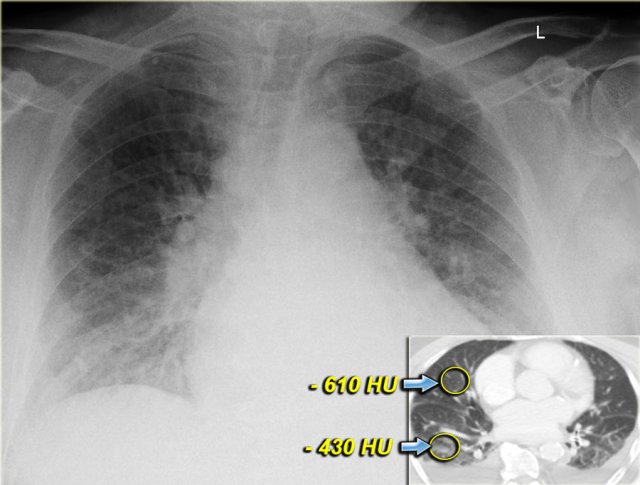

Both on the chest x-ray and on the CT the edema is gravity dependent and differences in density can be measured.

Notice that even within each lobe there is a gravity dependent difference in density.

This is only seen when the consolidations are the result of transudate like in CHF.

This is not seen when the consolidations are the result of exsudate due to infection, blood due to hemorrhage or when there is a capillary leak like in ARDS.